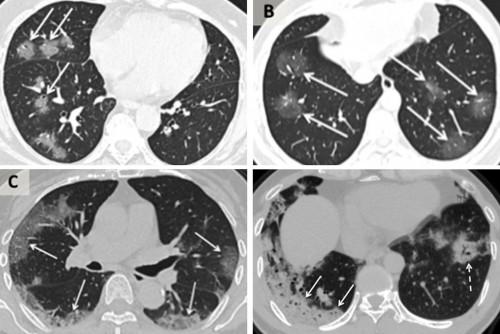

Μια πρόσφατη μελέτη από μια ομάδα ερευνητών της Ιατρικής Σχολής του Icahn στο Mount Sina διαπίστωσε ότι περισσότεροι από τους μισούς από τους 121 ασθενείς στην Κίνα είχαν κανονικές αξονικές τομογραφίες νωρίς στην ασθένειά τους. Η μελέτη και η εργασία του Δρ. Xiao δείχνει ότι καθώς η ασθένεια εξελίσσεται, οι αξονικές τομογραφίες δείχνουν «αχνά αχνά πράγματα», ένα είδος θολού μάτιου σε μέρη του πνεύμονα που είναι εμφανή σε πολλούς τύπους ιογενών αναπνευστικών λοιμώξεων. Αυτές οι αδιαφανείς περιοχές μπορούν να διασκορπιστούν και να διογκωθούν σε μέρη καθώς η ασθένεια επιδεινώνεται, δημιουργώντας κάτι που οι ακτινολόγοι αποκαλούν ένα μοτίβο "crazy paving" στη σάρωση.

Πηγή Νew York Times - Αξονικοί τομογράφοι ασθενών με κοροναϊό. Από δεξιά προς αριστερά 56χρονου θηλυκού, 44χρονου αρσενικού, 42χρονου αρσενικού και 65χρονου θηλυκού.